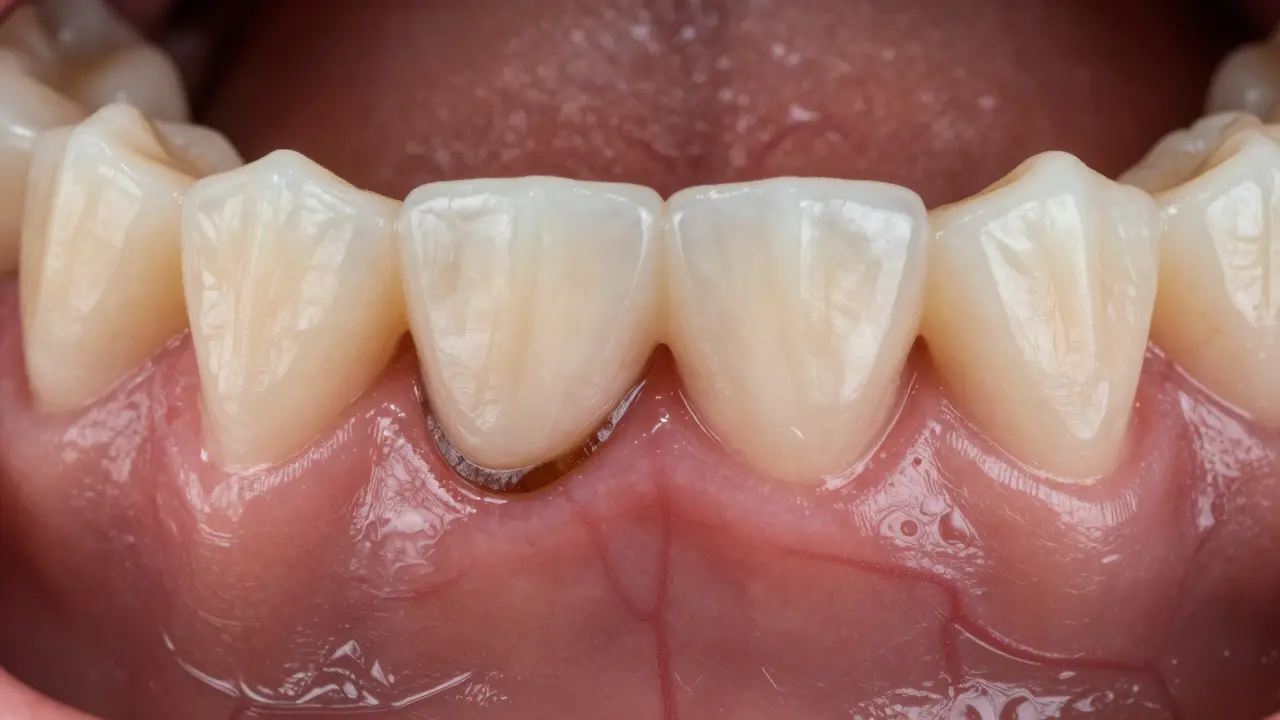

První krok je pravidelná návštěva zubaře – doporučuje se jednou za šest měsíců. Během kontroly dentista zkontroluje stav dásní a zubů a pokud najde zubní kámen, provede tzv. scaling. Skalování může být ruční (kovové nástroje) nebo ultrazvukové, kde vibrace rozbijí a odstrání tvrdý povlak.

Po odstranění kamene následuje leštění, které vyhladí povrch a ztíží bakteriím přichytit se znovu. Celý zákrok trvá obvykle 20–30 minut a není bolestivý – pokud máte citlivé dásně, můžete před návštěvou použít lokální anestetikum nebo si domluvit s dentistem jemnější techniku.